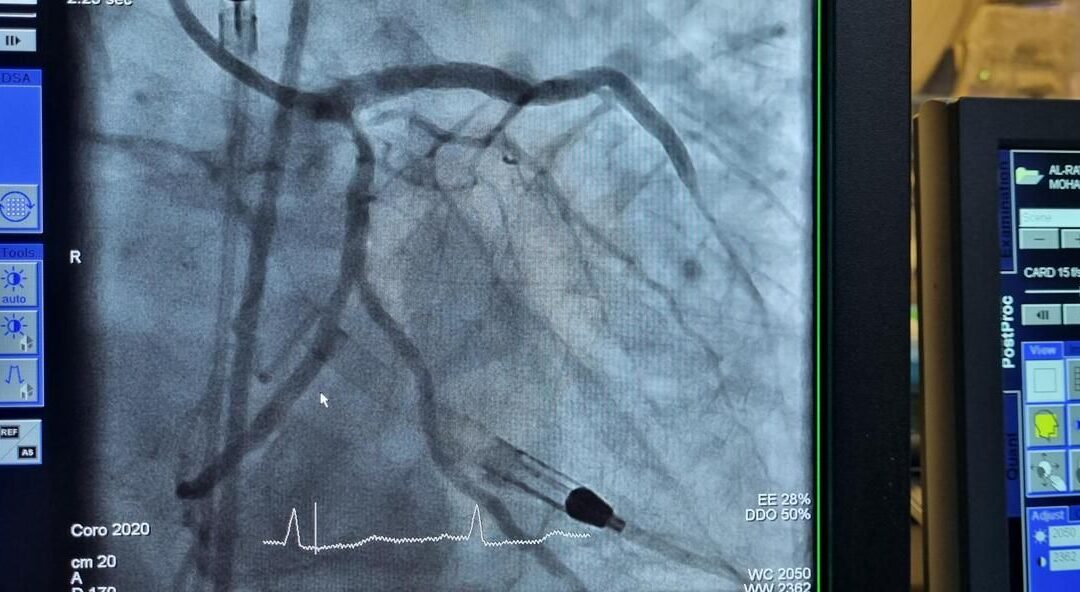

Successful High-Risk PCI in Complex STEMI Case — Powered by Impella® CP with SmartAssist®, at Hamad Medical Corporation, Qatar, Abiomed A 79-year-old male with multiple comorbidities—including hypertension, chronic kidney disease on dialysis, HFrEF, CLL, and a history...

Successful High-Risk PCI in Severely Calcified Coronary Artery Disease — Powered by Impella® CP with SmartAssist®, at Hamad Medical Corporation, Qatar A 60-year-old obese female presented with severe, diffuse coronary artery calcification involving: – 90%...